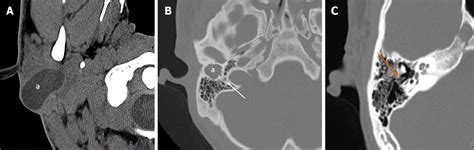

Diagnosing a cyst by the ear typically involves a physical examination by a healthcare professional. The doctor will examine the ear and surrounding area to assess the cyst's size, location, and any associated symptoms. In some cases, additional tests may be recommended, such as:

• Imaging tests: X-rays, CT scans, or MRIs may be used to get a detailed view of the cyst and surrounding structures.